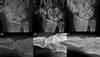

Figure 4 Clinical case of FCR Tenodesis transosseous T (Osseous grip) and Scaphoid excision. A and B. Preoperative wrist X-rays of SLAC stage II (AP and Lateral views). C and D. Postoperative wrist X-rays (AP and Lateral views) after 2 months. E and F. Postoperative wrist X-rays (AP and Lateral views) after 8.5 years. Source: Dr. Emmanouil Apergis. |

The transosseous FCR “T-technique” tenodesis was also performed using a volar harvest of a distally based FCR tendon strip, but differed in its method of fixation. Consistent with previously described osseous-anchorage variations of FCR tenodesis [10, 13], a transosseous tunnel was created through the triquetrum from volar to dorsal, enabling the tendon to be delivered dorsally through bone. The free tendon end was then redirected proximally and anchored to the dorsal distal radius, producing a rigid “T-shaped” construct with strong mechanical stability. This technique was chosen when more robust correction of midcarpal malalignment was required compared with ligamentous methods.